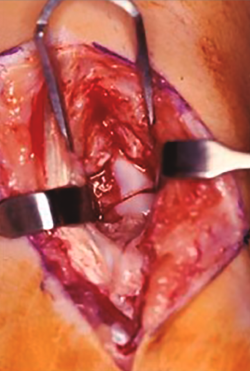

Figura 3. Visión fractura de escafoides por vía anterior.

Por vía abierta, podemos acceder por vía volar tal como describieron Russe en 1960(16) y Herbert en 1984(17). Se trata de un acceso relativamente fácil y adecuado a la lesión, que respeta al máximo la vascularización ósea; está indicada en las fracturas del tercio medio y tercio distal del escafoides. Nos permite una visión directa del foco de fractura controlando la reducción y la posterior síntesis (Figura 3).